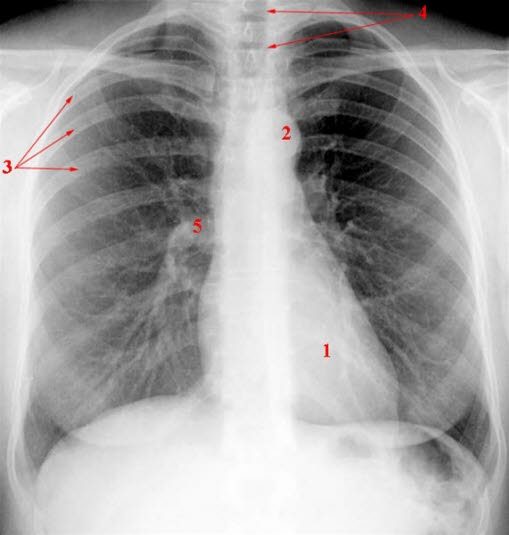

Normalt røntgenbilde av brysthulenBrystet omfatter brystkassen (thorax) med ribben, lunger med lungesekk (pleura), bronkier, og brystskilleveggen (mediastinum) som inneholder hjertet, store blodårer, luftrøret og spiserøret. På fagspråket betegnes røntgen av brystet som røntgen thorax.

Røntgen thorax avbilder lunger, lungesekk, hjerte og hovedpulsåren (aortabuen), mediastinum og de benede deler av brystkassen. Selv om dette er den hyppigst utførte røntgenundersøkelsen, kan den være en av de vanskeligste undersøkelsene å tolke. Ved normal undersøkelse finnes normalt utseende og normal posisjon av organene.

Rutinemessig vurderes lungene, midtre del av brystet, mellomgulvet, hjertet, posisjonen til hjertet og mediastinum, ribben, ryggsøylen. Røntgenlegen ser etter oppfylninger i luftrommene, sammenfall av lungevev, runde skygger (bl.a. svulster), utbredte små skygger (kreftspredning, metastaser), tegn til væske eller sykdom i lungehulen, forstørrede lymfeknuter eller svulster i mediastinum. Et betydelig antall sykdommer kan påvises, blant de viktigste er lungebetennelse i ulike varianter, fremmedlegemer i luftveiene (f.eks. hos småbarn), svulster, luftlekkasje til lungesekken (pneumothorax), lungetuberkulose, sarkoidose, støvlunge, sykdommer i den beinete delen av brystkassen, forstørret hjerte, hjertesvikt, tegn til klaffesykdom i hjertet.